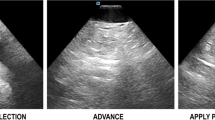

Advancing the ICE Catheter to the Heart (Fig. 11.1)

(Panel a) Arrow s howing lumen in the path of the ICE catheter, which allows safe advancement forwards towards the right atrium. (Panel b) Arrow showing soft tissue in the path of the ICE catheter. In this situation, clockwise or counterclockwise torque is needed to show lumen prior to advancing the ICE catheter

In order to place the ICE catheter in the heart safely without fluoroscopy, the probe is advanced from the femoral vein to the RA while ensuring that lumen is present in the path of the probe. This is done by visualizing “black lumen” on the top right of the ICE display (i.e., in front of the probe). If tissue is encountered, the probe can be gently withdrawn and a clockwise or counterclockwise torque can be applied to show lumen, and the probe can be advanced again.

In some instances, a branching point is identified, and the probe can be anteriorly-flexed towards the main branch of the vein to allow it to pass towards the heart. Care should be taken not to advance the probe against resistance.